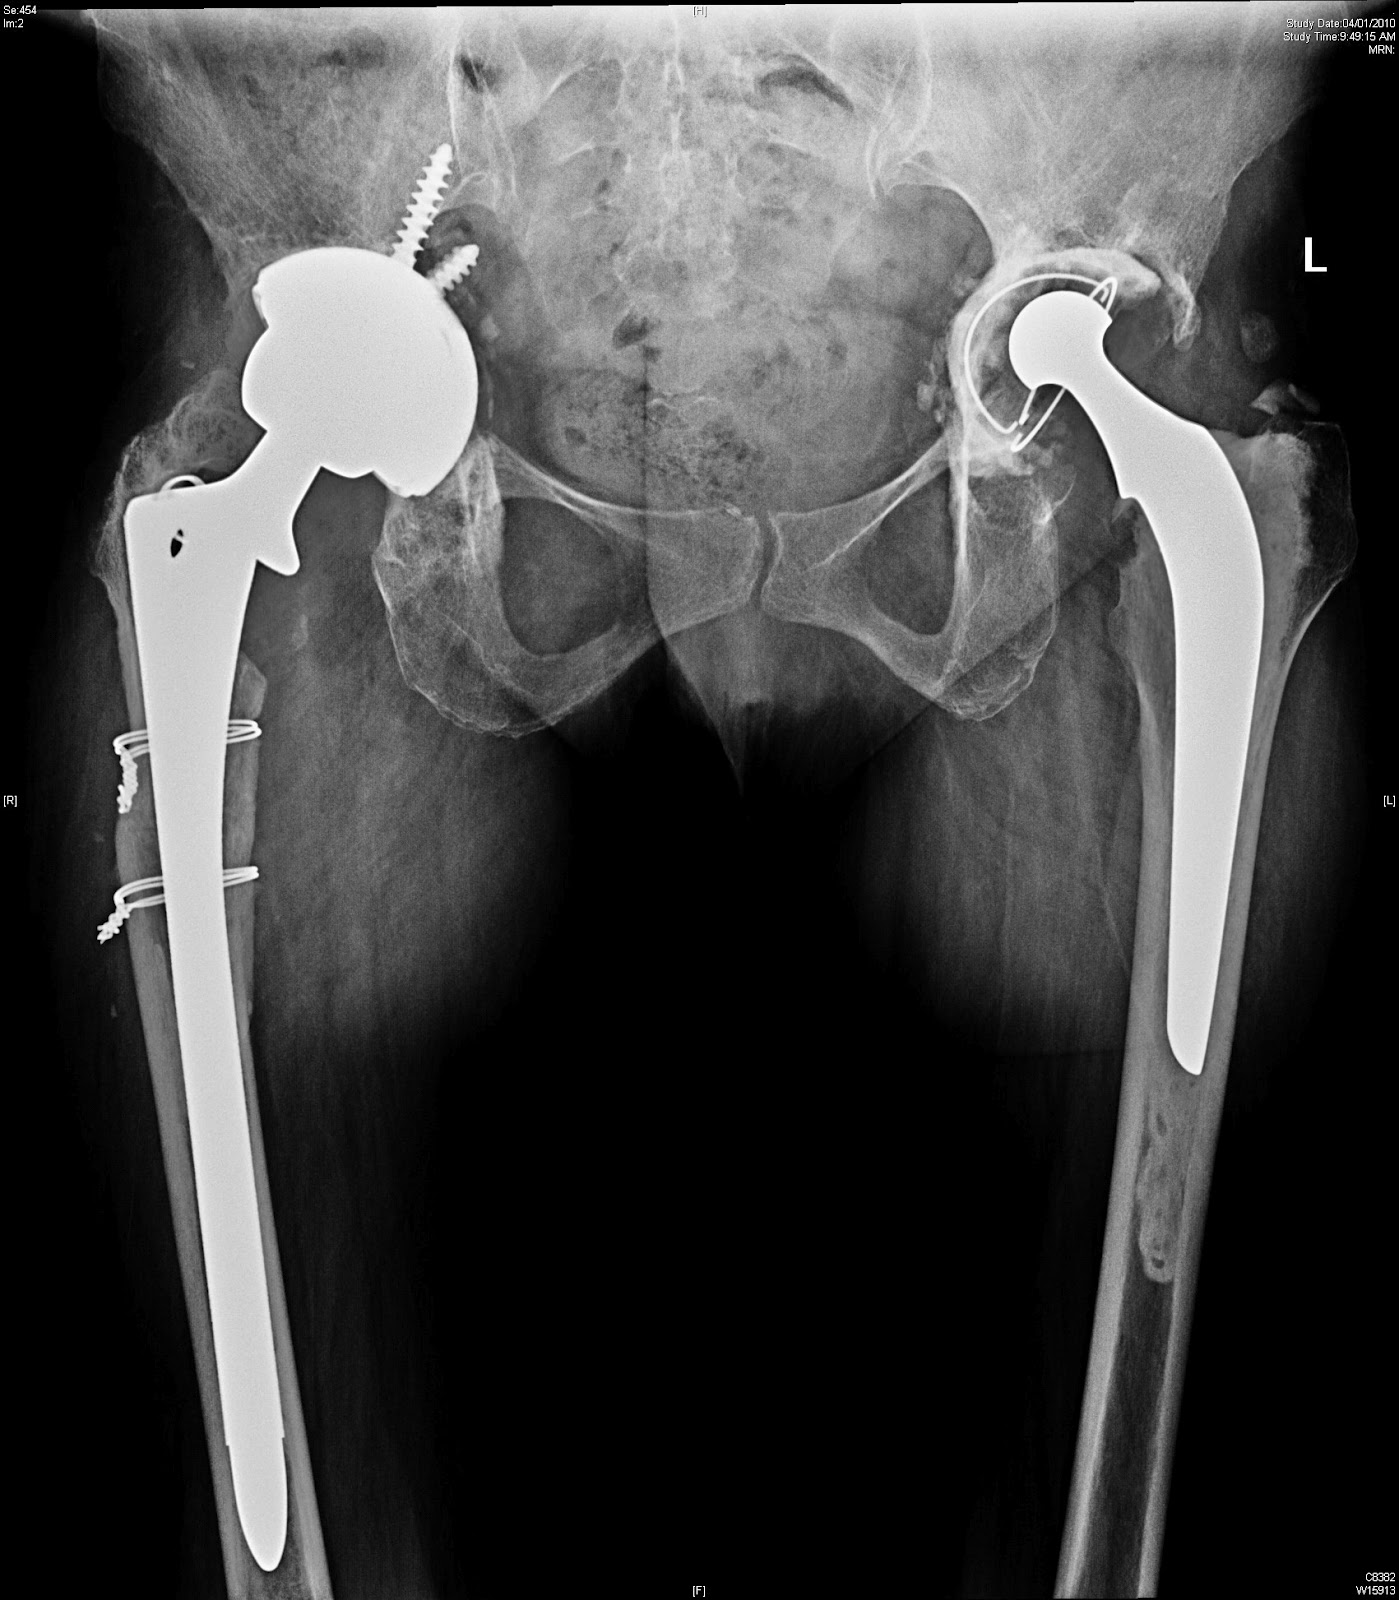

Below is a similar case I discussed before, So far I could trace only the preop and one post op at 3 months. will trace the entire series in a few days once I get back to get the whole story.